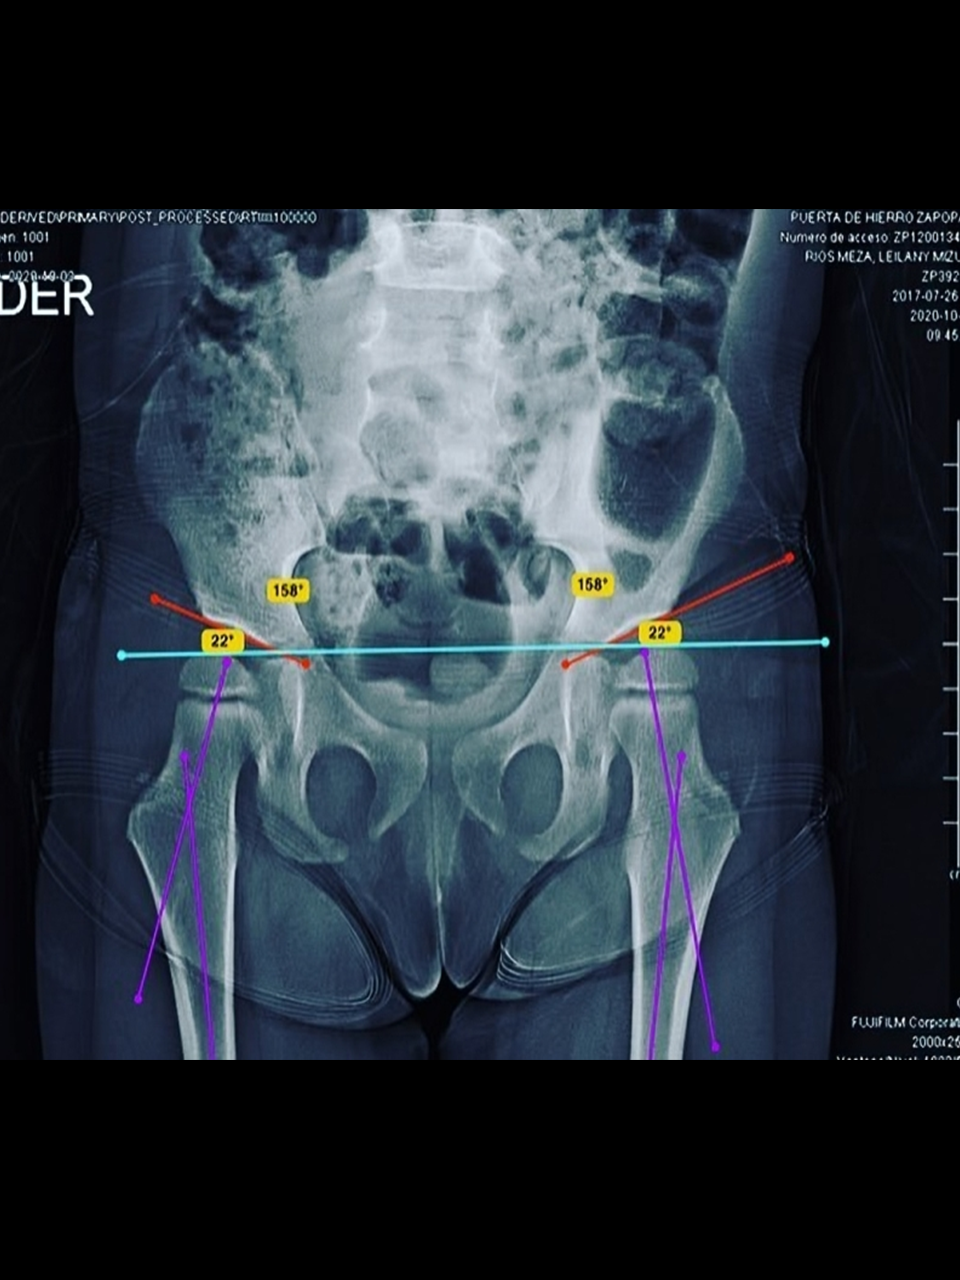

• Deformidades torsionales de tibia y fémur

• Displasia del desarrollo de cadera y tamiz de cadera